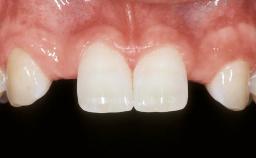

| Jaw | Maxilla |

| Area | Posterior |

| # of Teeth | 2 |